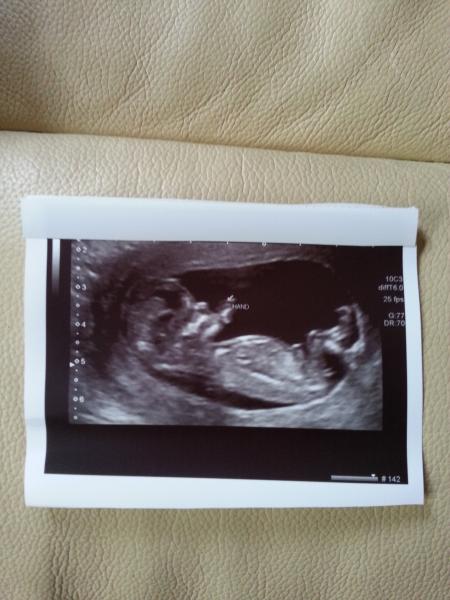

Baby was wriggling and waving and generally being a pain for the sonograher.

All is good, am now 12 weeks 1 day and my nuchal measurement was between 1.0 and 1.5 mm, she measured it 3 times as baby wasn't still for that long!

Scan this morning, all good, just the one and a right little cutie poser waving away Smile great to see all the good news coming in. Hope you're all well. My EDD is now the 10th, not the 16th!